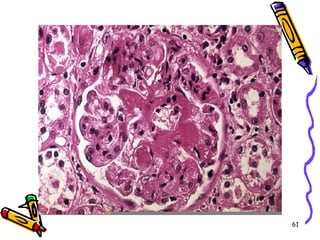

Mikroskobi

• Damar duvarında nekrotizan

inflamasyon birlikte lökositoklasis

• Böbreklerde fokal segmental

nekrotizan glomerülonefrit-şiddetli

diffüz kresentik glomerülonefrit

• İmmün kompleksler görülemez (pauci-

immune)